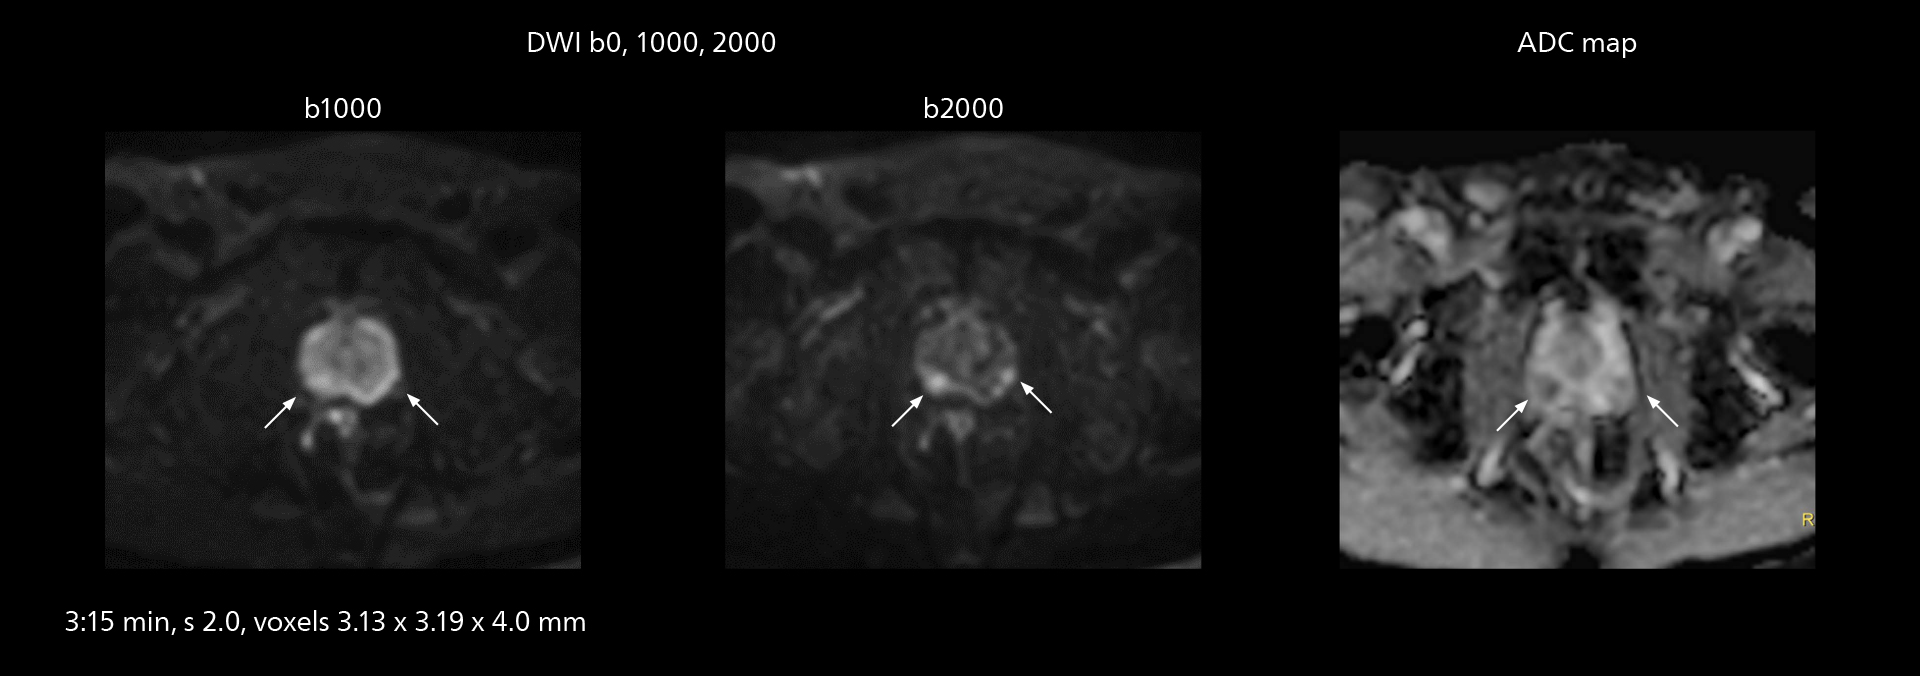

Diffusion studies benefit from powerful gradients

The high performance of the Vega HP gradients is particularly impressive in DWI. “The Vega HP gradients enable us to scan faster and use b-values as high as 2000, for example in prostate DWI and in DWIBS, which provides image quality that is remarkably improved over the previous system and we are able to more easily see lesions.”

MRI of prostate

Examples of prostate imaging showing faster scan times and improved resolution illustrate the power of SmartPath to Elition X in this case of prostate cancer with PI-RADS score 4.

MRI of prostate

Examples of prostate imaging showing faster scan times and improved resolution illustrate the power of SmartPath to Elition X in this case of prostate cancer with PI-RADS score 4.

The value of the Elition X gradients is also evident in DWIBS studies. “The fact that we can consistently obtain distortion‐free DWIBS while reducing imaging time at three coronal stations is excellent,” Dr. Makuuchi says. “In these patients, it’s also important that the application of Compressed SENSE to T2‐weighted, STIR and mDIXON sequences has no impact on the examination time of whole‐body imaging. As a result of the increased speed and higher image quality we realize, DWIBS studies have now become routine examinations.”

Fast whole body DWIBS examination

With SmartPath to Elition X the team can obtain excellent quality DWIBS imaging and reduce imaging time. Other sequences also fit in the examination slot. This case shows left paravertebral neurogenic tumor and Th10 vertebral hemangiomas.

Fast whole body DWIBS examination

With SmartPath to Elition X the team can obtain excellent quality DWIBS imaging and reduce imaging time. Other sequences also fit in the examination slot. This case shows left paravertebral neurogenic tumor and Th10 vertebral hemangiomas.